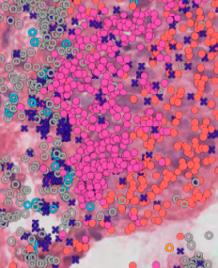

The retina, a light-sensitive layer at the back of the eye, is responsible for processing light signals crucial for vision. With multiple sublayers and cell types, it is one of the most intricate structures in the human body. Eye care health professionals use a variety of imaging techniques in order to assess its structure and function. Central (Figure 1A)

and wide-field (Figure 1C) photographs capture en face views of the retina, while cross-sectional scans, such as optical coherence tomography (OCT), reveal retinal sublayers (Figure 1B). Different wavelengths of light can also be used to infer retinal health and metabolism (Figures 1D and 1E).

Figure 1: A healthy retina imaged by different modalities. (A) Photograph of the central retina. (B) Optical coherence tomography, demonstrating various retinal sublayers. (C) Widefield pseudocolour photograph. (D) Fundus autofluorescence image of the central retina using short-wavelength light. (E) Fundus autofluorescence image of the central retina using near-infrared light.

AI has already shown promise – for example, in Stargardt disease, where bright hyperautofluorescent flecks are a key clinical feature. AI algorithms have been utilised to automatically detect and outline these flecks, with accuracy approaching that of expert clinicians. This demonstrates not only the feasibility of AI in IRD, but also its potential to accelerate and scale diagnostic processes. There has also been a rise in XAI, particularly in healthcare, where transparency and trust are as important as accuracy. By opening up the ;black box’ of AI, XAI helps clinicians to understand why an AI model makes particular predictions. This allows better translation of complex data into meaningful patient care.

Figure 2: Example of artificial intelligence (AI)-facilitated segmentation of hyperautofluorescent flecks in Stargardt disease. (A) Short-wave autofluorescence image of an eye with Stargardt disease. Pointers indicate examples of hyperautofluorescent flecks. (B) Flecks segmented by an AI algorithm. (C) Manually segmented flecks.